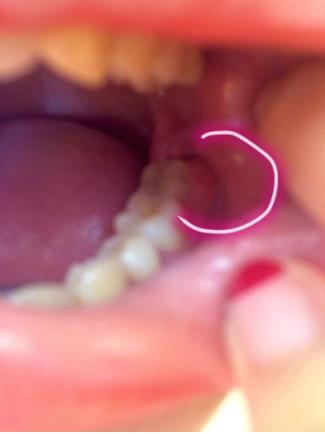

智齿生长的位置特殊,给它的清洁和治疗带来许多问题,常引起的疾病有龋齿(俗称蛀牙)、牙周炎、牙髓炎。由于智齿在最里面,日常刷牙不容易清洁,容易产生蛀牙,且智齿往往由于萌发空间不足出现胀痛,还会侵犯邻牙,造成牙疼。由于没有对咬牙,有时智齿会过度萌发伸长,进而影响咬合;还有时会萌发不足成为阻生齿,引起牙列不齐,冠周间隙感染,张口困难。

5、如果智齿经常疼,而且疼的比较厉害,可能已经引发牙冠周软组织发炎,所以导致智齿肿胀、疼痛;再如果智齿长的位置很歪,影响其它牙齿正常咀嚼,也影响美观,最好是考虑拔牙。拔牙前提是确保牙冠周围没有炎症,才能安排拔牙,免除后顾之忧,拔智齿是拔牙里最难的一种,所以一定要到正规口腔医院,请正规医师进行专业拔牙。